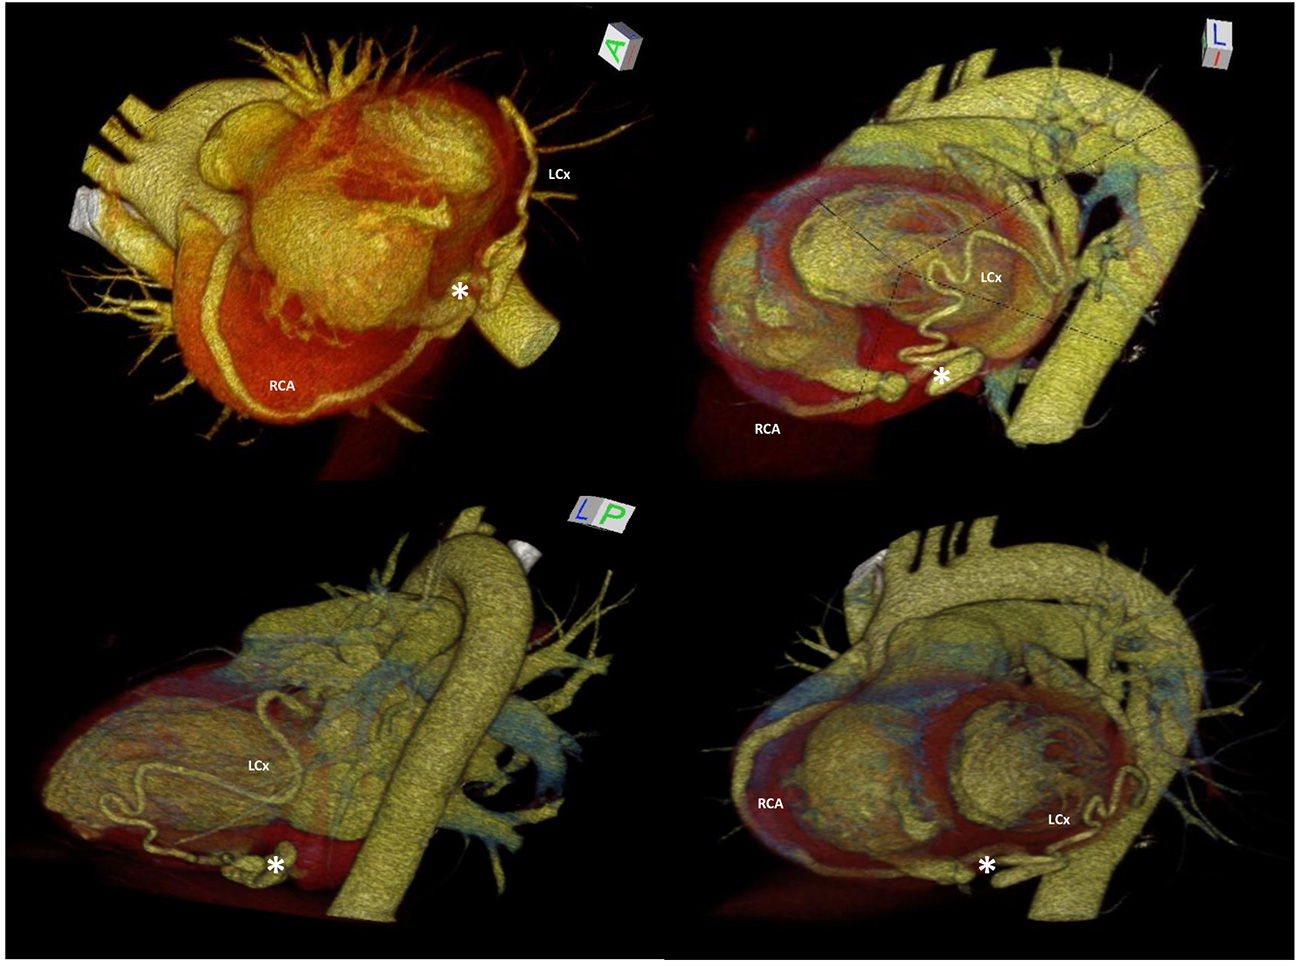

Figure 2

3D-MDCTA volume-rendering reconstruction showing dilated and tortuous right coronary artery and left circumflex artery forming at the base of the heart a distal anastomosis (white asterisk), followed by drainage into the right ventricle through the posterior-lateral wall. 3D-MDCTA, three-dimensional multidetector computed tomography angiography; LM, left main coronary artery; RCA, right coronary artery; LAD, left anterior descending; LCx, left circumflex.

Three-dimensional multidetector CT angiography (3D-MDCTA) confirmed the presence of severely dilated and tortuous distal RCA and LCx (Supplementary Video 1) and precisely defined entry point of the distal right coronary fistula and two drainage sites draining into the a round-shaped chamber within the right ventricle (Figures 1D,E, Figure 2).